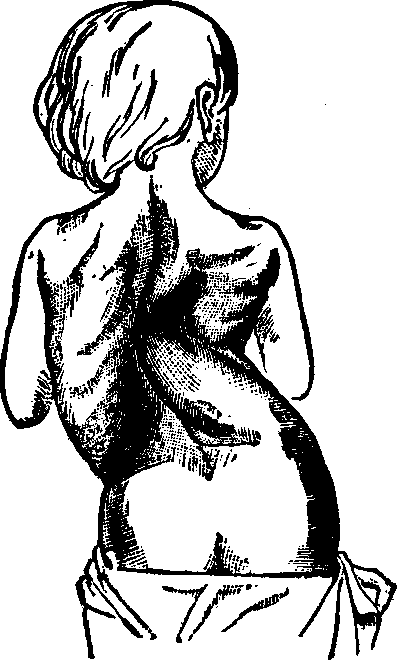

Symptoms. The sufferer from leucorrhea becomes pale and emaciated, the eyes dull and heavy, the functions of the skin, stomach and bowels become deranged, more or less pain in the head is experienced, sometimes accompanied with dizziness, palpitation is common, and, as the disease progresses, the blood becomes impoverished, the feet and ankles are swollen, the mind is apprehensive and melancholy, and very frequently the function of generation is injured, resulting in complete sterility. Exercise produces pain in the small of the back and the lower portion of the spine, and, owing to a relation of the vaginal walls, the womb falls far below its natural position, or turns in various directions, according to the manner in which the weight above rests upon it. Ulcers are apt to appear upon the mouth of the womb, the matter from which tinges the discharge and stains the linen. Hysteria is often an attendant of this disease.